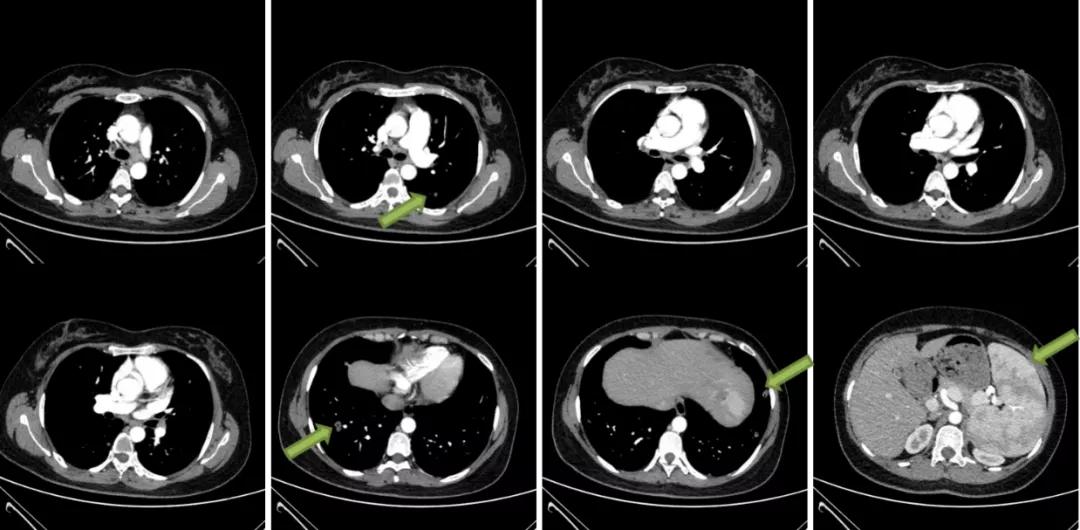

胸部CT平扫+增强三维:1、双肺多发结节,突出病灶位于右肺下叶外基底段和左肺下叶前基底段。2、纵隔淋巴结肿大。3、肝脏钙化灶。4、右肾结石。5、脾大。双肺多发实性结节、玻璃结节,最大者位于右肺下叶外基底段(IM177),长径约1.7cm,边缘浅分叶,周围多发毛刺,内见含气支气管影。纵隔内可见数枚肿大的淋巴结。心脏大小未见明显异常,心包未见明显积液。双侧胸腔未见积液,胸膜未见增厚。肝内斑点状致密影,右肾结节状致密影,脾脏体积增大。

图7:胸部CT平扫+增强三维(2020/11/5)